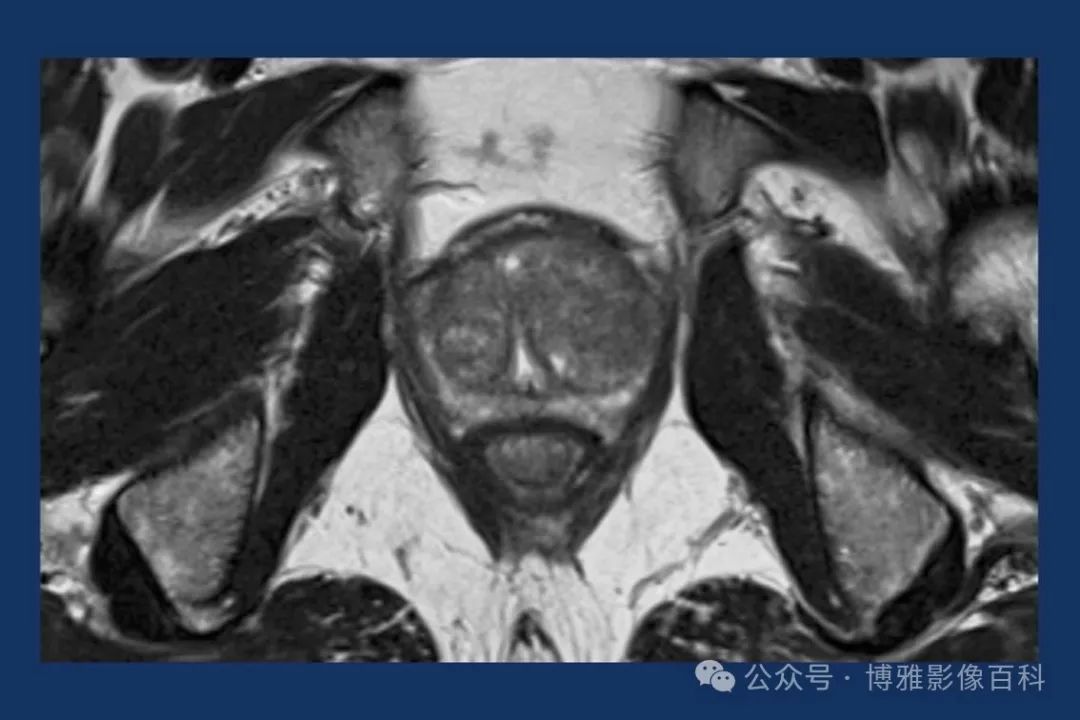

MR 解剖学

前列腺良性增生患者的轴向T2 图像,其他方面正常。外周带是一薄层均匀的高信号,边界清晰连续性的低信号包膜。移行带通常表现为不均匀中等信号,病灶被边界清楚的BPH良性前列腺增生结节所取代。精囊具有均匀T2高信号。未见淋巴结肿大。